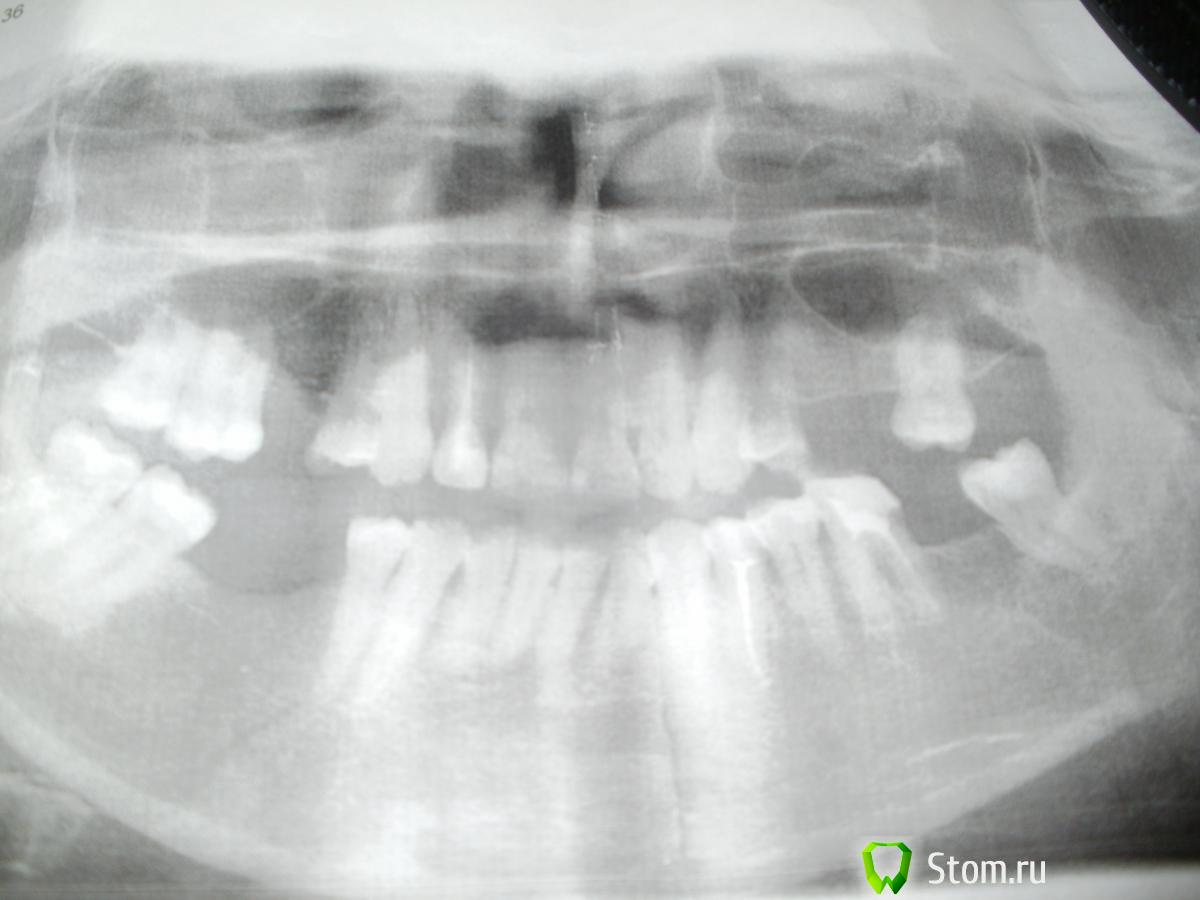

Людмила 777 Опубликовано 19 января, 2012 Поделиться Опубликовано 19 января, 2012 извините, если я не правильно сформулировала тему, вероятно оба процесса это одно и то же. меня же интересует следующее - отсутствуют 6 боковых зубов в разных местах, варианты, предложенные различными врачами, следующие:1) депульпировать все близрасположенные зубы ( а на данный момент депульпировать придётся действительно все, как это ни печально, и поставить коронки, мосты - я не очень помню названия - таким образом придётся депульпировать 7 или 8 зубов )2) поставить 4 самых необходимых импланта и на этом пока завершить процессПервый вариант пугает тем, что живые зубы придётся превращать в мёртвые + вероятность возникновения кисты после того, как поставлены коронки - к сожалению, у меня такое уже было - плохо запломбированный канал в клинике супер экстра класса, потом киста, потом перелечивание, временные пломбы и т.п. - в общем, вы сами знаете, как это может быть...Второй - страшно, что не приживутся и ещё, конечно, страшно попасть к непрофессионалу, столько плохих отзывов о разных клиниках в интернете.Но... решаться на что-то надо. Всё-таки, что предпочтительнее на ваш взгляд профессионалов? Ссылка на комментарий

Bier Опубликовано 19 января, 2012 Поделиться Опубликовано 19 января, 2012 снимок покажите Ссылка на комментарий

Людмила 777 Опубликовано 20 января, 2012 Автор Поделиться Опубликовано 20 января, 2012 Ссылка на комментарий

x3m Опубликовано 23 января, 2012 Поделиться Опубликовано 23 января, 2012 снимок, мягко говоря, не очень.конечно же вариант 2 лучше но без лечения каналов, штифтов и коронок Вы не обойдетесь. в этой теме Вы можете спросить рекомендации Ссылка на комментарий